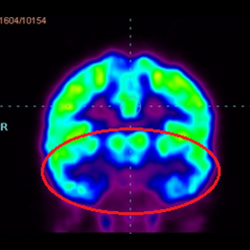

細(xì)胞治療前PET CT掃描顯示神經(jīng)組織中的藍(lán)/黑色區(qū)域,表明腦癱引起的大腦損傷。

腦癱細(xì)胞療法, 腦癱治療

細(xì)胞治療后,藍(lán)色和黑色區(qū)域減少,并且看到更活躍的區(qū)域。這表明損傷減少并改善了大腦功能。